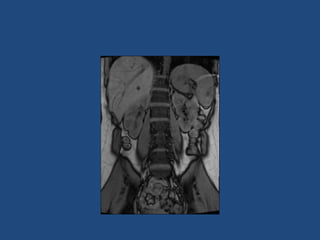

Imaging

>6cm high suspicion of malignancy

3-6cm repeat imaging in 3-6M

Delayed washout on contrast is suggestive

most are often inhomogeneous, irregular

margins

• Look for invasion of IVC

• Always do CAP and consider bone scan and

pet if in doubt

• Don’t ever biopsy (tumour spill)